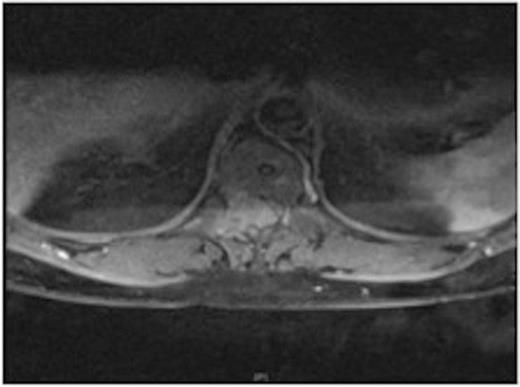

MRI showing the T10-11 extra-dural tumour with erosion of the T12 pedicle

On review of the original thoracic CT scan, which was performed 2 months prior to the MRI, the tumour was distinguishable but, as the spine is such a rare location for carcinoid metastasis, it was initially unreported.